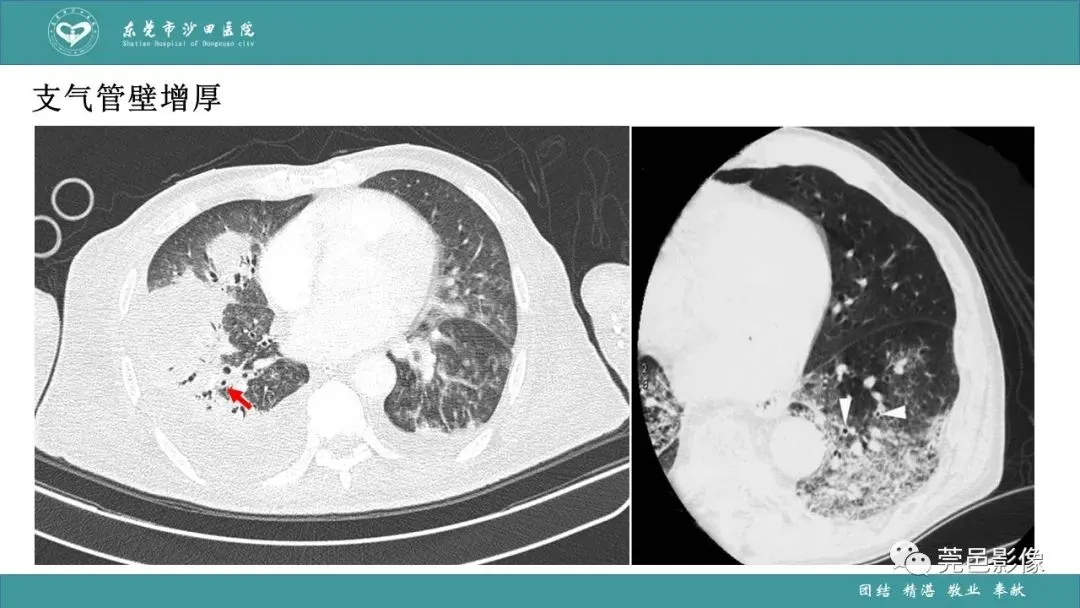

>课件 | 肺炎克雷伯杆菌肺炎影像学诊断与鉴别诊断

课件 | 肺炎克雷伯杆菌肺炎影像学诊断与鉴别诊断